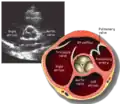

Parasternal short axis (PSAX)

This view is obtained in the same window as the parasternal long, but with the probe rotated 90°. In this view, the aortic valve is seen in cross-section with the right ventricular inflow & outflow tracts visible with the tricuspid valve as well. Pulmonary valve is not visible in this view. Both the right and left atria are visible.

- Aortic valve in short-axis

- Aortic valve dysfunction, aortic sclerosis/stenosis

- Aortic valve area by planimetry